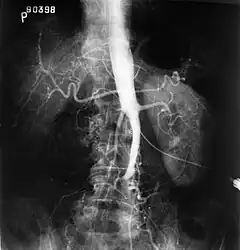

The physical examination usually shows weakened femoral pulses and a reduced ankle-brachial index. The diagnosis can be verified by color duplex scanning, which reveals either a peak systolic velocity ratio ≥2.5 at the site of stenosis and/or a monophasic waveform. MRA and multidetector CTA are often used to determine the extent and type of obstruction. Another technique is digital subtraction angiography which allows verification of the diagnosis and endovascular treatment in a single session.[8]

Angiography provides important information regarding the perfusion and patency of distal arteries (e.g. femoral artery). The presence of collateral arteries in the pelvic and groin area is important in maintaining crucial blood flow and lower limb viability. However, angiography should only be used if symptoms warrant surgical intervention.[8]

- Fluoroscopic image of an affected aorta